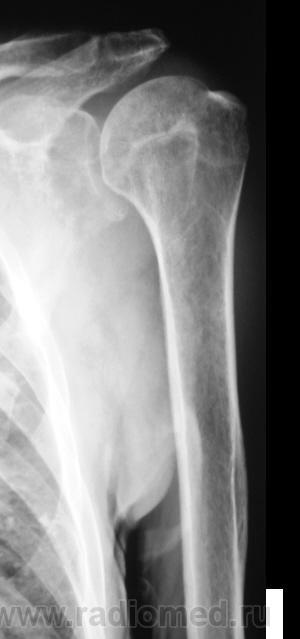

Лаборанты проводили исследование согласно стандарту, хорошие лаборанты, а это значит, что рентгенологически пациент будет "добит", и будет передан по назначению, даже без врача-рентгенолога. Когда я появился в кабинет исследование было закончено.

Иллюстрации ниже.

Рентгенограммы в стандартных проекциях - прямая и боковая.